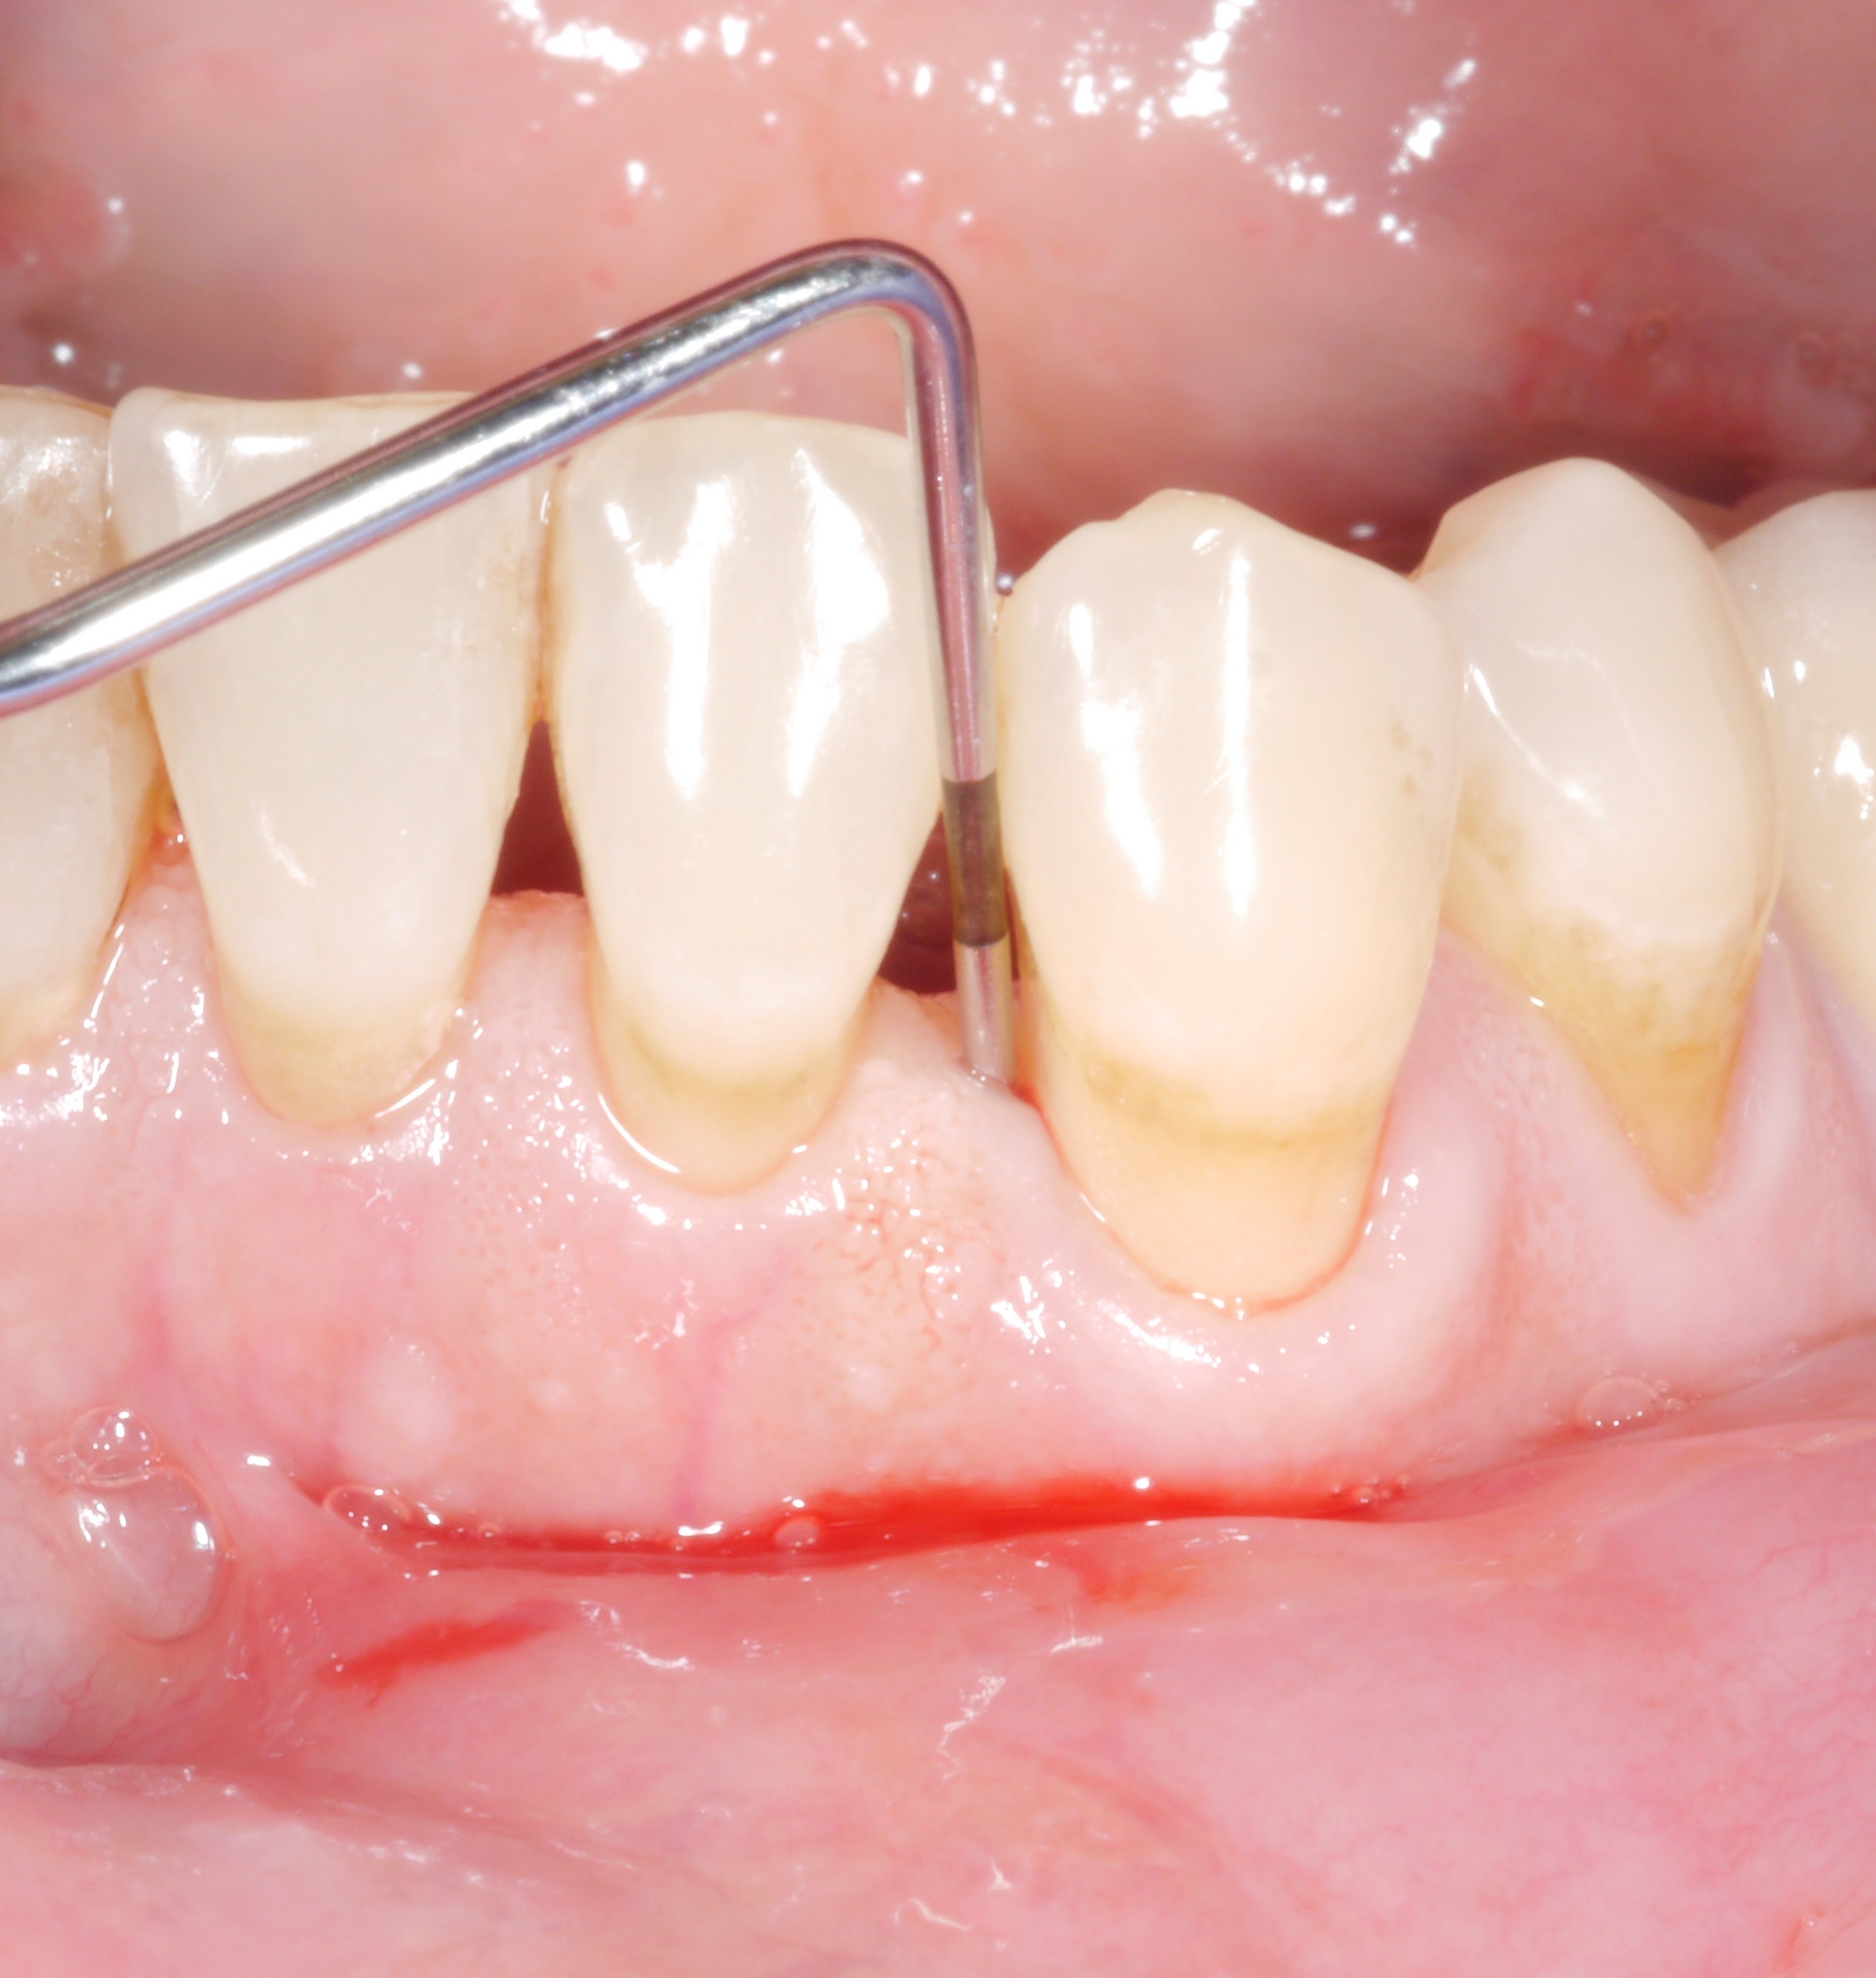

A residual pocket probing depth of 6 mm – is it a problem?

It is a situation we are all too familiar with: following the active phase of treatment, nearly all the patient’s teeth are now unaffected by increased pocket probing depths. However, there are still 1 or 2 places where the treatment goal has unfortunately not been achieved. The following thought might arise: “how bad can it be? A single pocket of 6 or 7 mm – surely that can’t make a big difference?”

However, dentists should not rush to say they are content with residual pocket probing depths. This is because even individual residual pocket probing depths of more than 4 mm constitute a problem, as least in the longer term – both for the affected tooth and for the rest of the dentition.

- Bleeding on probing doubled the risk of later tooth loss.